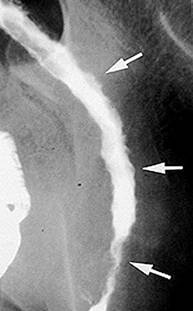

Examenul baritat cu dublu contrast evidentiaza ulceratiile aftoide sub forma unor mici depozite de substanta de contrast inconjurate de un halo transparent. Mai pot fi evidentiate leziuni unice sau multiple despartite de zone sanatoase- aspectul de "pietre de pavaj", stenoze pana la "semnul sforii", fistule. Cand exista suspiciunea de stenoza, examenul baritat este contraindicat.

Boala Crohn- ulceratii extensive Semnul

sforii in boala Crohn

ale peretelui colonului, inflamatia mucoasei ileala